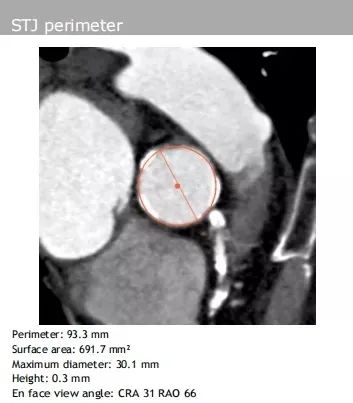

窦管交界处:平均直径29.7 mm、周长93.3 mm

根据影像学检查结果,最终决定采用右股动脉为主入路,选择22 mm预扩球囊及植入VitaFlow TAV27 mm生物瓣膜。